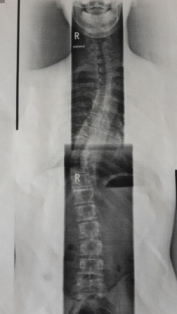

- Rechtskonvexe Thorakolumbale Skoliose von 28 Grad (Bild im Anhang)

Ansicht von vorne

20151219_150853.jpg (26.85 KiB) 10493 mal betrachtet

20151219_150925-1.jpg (28 KiB) 10493 mal betrachtet

Wie Lady S sagte: Kann sein oder auch nicht sein. Der Verlauf ist bei jedem unterschiedlich und schwer vorherzusagen. Eine extreme Verschlechterung in kurzer Zeit, wie dies in der Jugend bei Wachstumsschüben passieren kann, ist unwahrscheinlich. Bei einer Verkrümmung ab 30° im Erwachsenenalter tritt nach Erfahrungswerten durchschnittlich eine Verschlechterung von 1° pro Jahr auf. Es gibt aber Erwachsene, bei denen das nicht passiert und welche, bei denen schlimmere Verschlechterungen auftreten. Verschlechterungen bei einer Skoliose unter 30° sind nicht so häufig, aber auch nicht auszuschließen. Du kratzt so gerade an dieser 30°-Grenze - vor allem sind die Messwerte immer etwas ungenau, sodass man von einer Messtoleranz von 5° ausgeht; hinzu kommt, dass bei dir offenbar Teilaufnahmen gemacht und übereinander gelegt wurden (oder seh ich das falsch?), was noch mehr zu Ungenauigkeiten führen kann.

Als neue Diagnosen kam hinzu, dass ich einen Flachrücken habe. (Max. Kyphosewinkel 41,1Grad und max. Lordosewinkel 23,4 Grad)

Er hat auch nochmal meine Krümmung nachgemessen und auch meine Gegenkrümmungen.

Hauptkrümmung: Thorakolumbal rechtskonvex 28 Grad Rotation: II

Gegenkrümmung: Thorakal links 28 Grad Rotation: I

Gegenkrümmung: Lumbal links 13 Grad Rotation: I